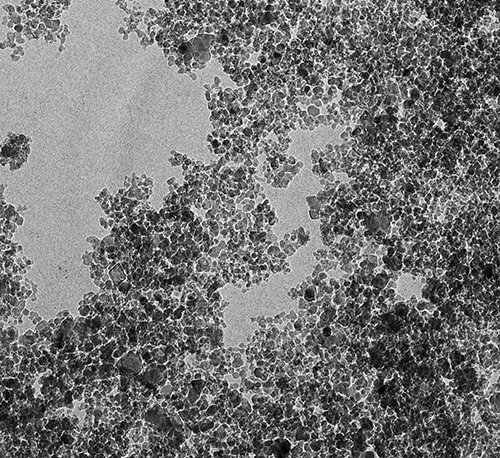

— Любой обычный лекарственный препарат действует не только на место локализации заболевания, но и на весь организм в целом, оказывая на него токсическое воздействие. Мы ищем пути снижения токсичности и дозировки лекарств и возможности сделать их действие более направленным, — объяснил ученый. Было необходимо найти специальные транспортировщики, которые доставляли бы препарат прямо к пораженным клеткам, минуя здоровые. С течением времени решение нашлось: наночастицы. На данный момент существует около 400 видов наночастиц, которые создают из различных материалов. Ученые обратили особое внимание на детонационные наноалмазы благодаря уникальному набору их химических и биологических свойств. Особенно важно, что наноалмазы нетоксичны и биосовместимы с организмом. Наноалмаз состоит из частиц атомов углерода, собранных в алмазную решетку. Частицы имеют размер около пяти нанометров, а их поверхность насыщена функциональными (химическими) группами, с помощью которых можно прикреплять лекарственные вещества к поверхности частиц наноалмаза. Главным открытием в процессе исследованийстал тот факт, что при прикреплении к частицами наноалмаза лекарственного вещества последнее в ряде случаев не только усиливает свое терапевтическое действие, но и приобретает новые фармакологические эффекты, ранее неизвестные для нативного (неприкрепленного) лекарственного вещества. Так, известный препарат «Глицин» при создании системы его доставки с наноалмазом обнаружил совершенно новые, неизвестные ранее фармакологические эффекты. Самым значимым из них является снижение смертности при инсульте и тяжести побочных эффектов в постинсультном периоде. В один день нами было подано восемь патентных заявок на новые эффекты «наноглицина». Также ведется активный поиск новых усиленных фармакологических эффектов других веществ при их прикреплении к наноалмазу. Например, мы пытаемся разработать системы доставки лекарственных веществ против таких социально значимых заболеваний, как туберкулез и отложение солей пирофосфата кальция (псевдоподагра).